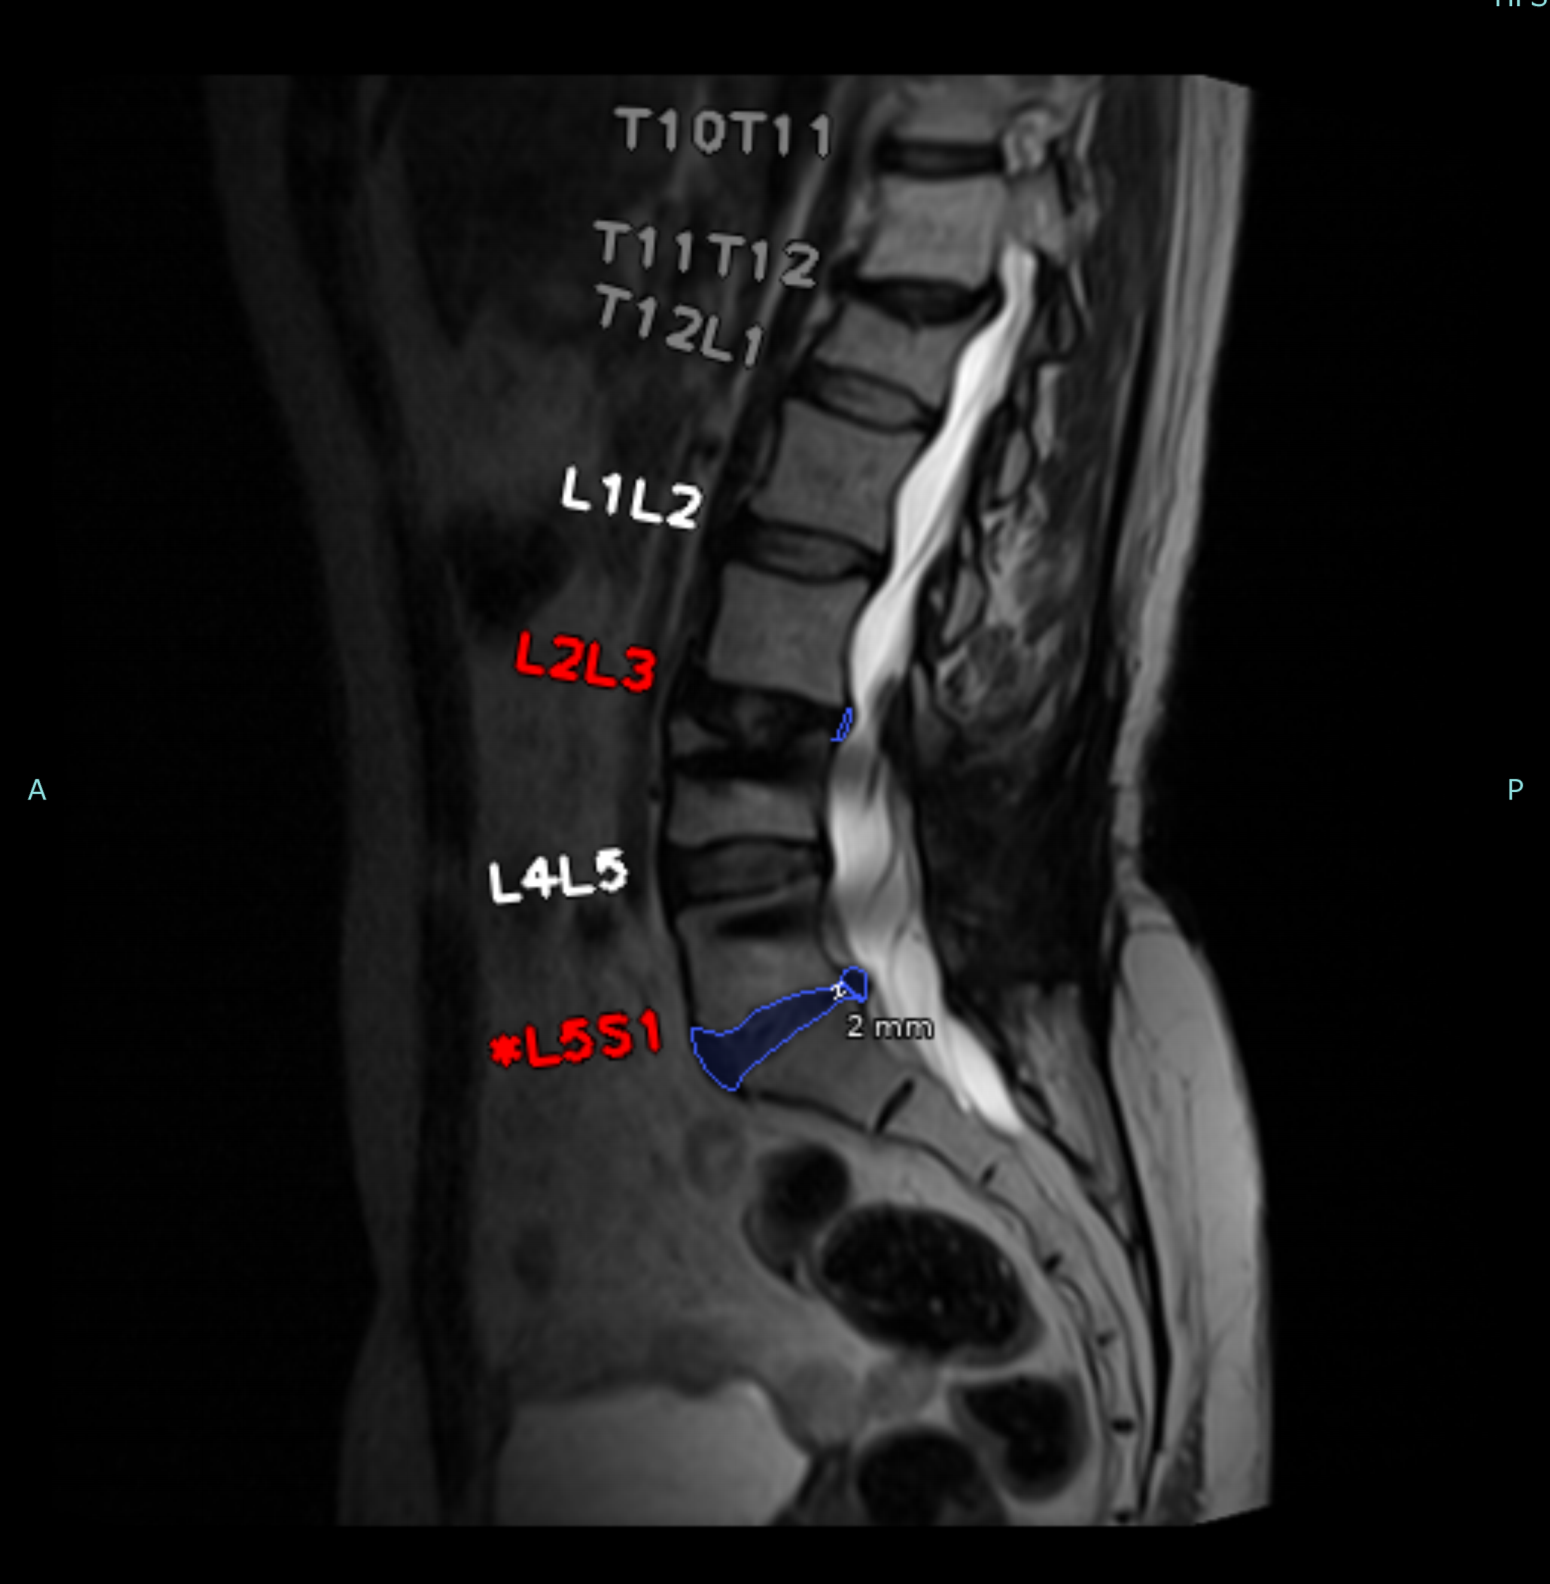

IA para Resonancia Magnética Lumbar

Esta solución impulsada por IA proporciona mediciones automáticas y objetivas para patologías de columna lumbar, facilitando diagnósticos más consistentes.

Hernia, protrusión y extrusión discal.

Estenosis espinal central y congénita.

Impacto radicular y alteraciones vertebrales.

Mediciones objetivas de lordosis y diámetro aórtico.